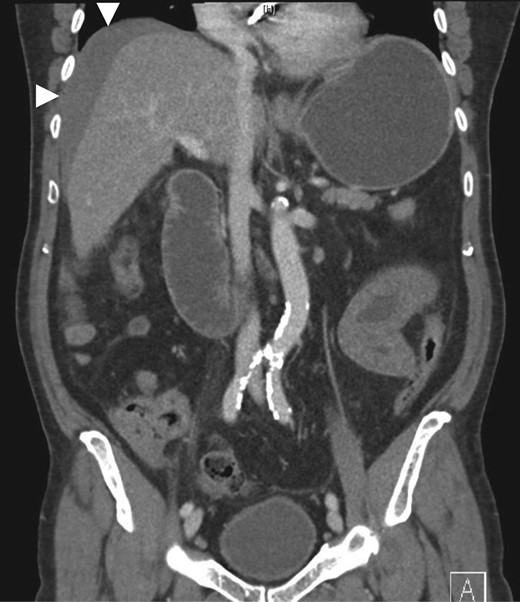

Coronal (A, C), sagittal (B) and axial (D) CT showing small bowel intramural haematoma up to the mid-ileum with associated oedema causing obstruction and proximal small bowel and gastric dilatation.

Non-contrast abdominal CT is the most valuable imaging modality. Diagnostic features include circumferential bowel wall thickening, intramural hyperdensity, luminal narrowing and intestinal obstruction [2]. Ultrasound is non-specific and may show intra-abdominal free fluid and intestinal wall thickening with an echogenic submucosa [2, 8].